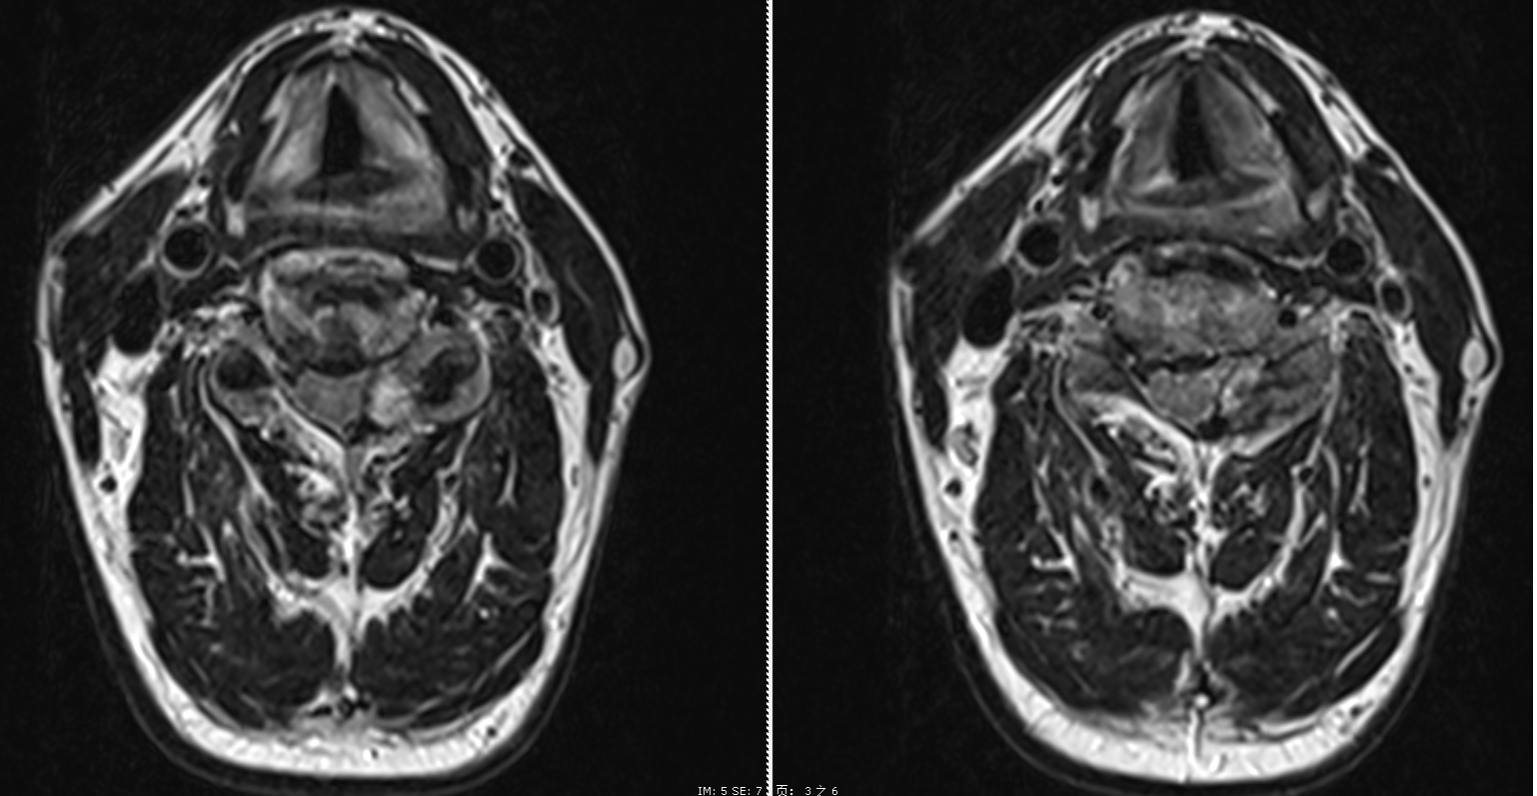

手術(shù)過程中,醫(yī)療團(tuán)隊(duì)?wèi){借精湛的技術(shù)和默契的配合,成功為患者解除了神經(jīng)壓迫。術(shù)后,患者癥狀得到顯著緩解,復(fù)查MRI結(jié)果顯示脊髓壓迫已完全解除,脊髓膨隆狀態(tài)良好。患者術(shù)后僅一天便能下床活動,三天后順利出院。術(shù)后兩周隨訪,患者的疼痛癥狀已經(jīng)完全消失,基本恢復(fù)正常的日?;顒印?/span>

術(shù)后第一天MRI圖像